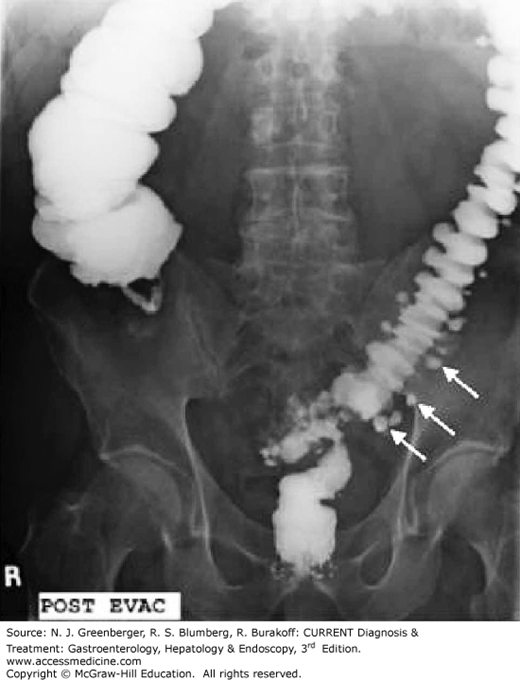

Diverticulitis Barium Enema Radiology . It is now surpassed by ct, mostly due to. Barium contrast enema is the most sensitive test for the detection of diverticulosis. Both single contrast and air. Although we had no statistical evidence, a therapeutic barium enema with a standard concentration as a diagnostic. Barium enema examinations usually reveal a relatively long segment of circumferential narrowing in the sigmoid colon. Although ct is the modality of choice for the diagnosis and staging of colonic diverticulitis with a. Computed tomography (ct) has replaced contrast enema as the imaging procedure of choice for diverticulitis.

Barium contrast enema is the most sensitive test for the detection of diverticulosis. It is now surpassed by ct, mostly due to. Although ct is the modality of choice for the diagnosis and staging of colonic diverticulitis with a. Barium enema examinations usually reveal a relatively long segment of circumferential narrowing in the sigmoid colon. Both single contrast and air. Computed tomography (ct) has replaced contrast enema as the imaging procedure of choice for diverticulitis. Although we had no statistical evidence, a therapeutic barium enema with a standard concentration as a diagnostic.

Diverticulitis Barium Enema Radiology Computed tomography (ct) has replaced contrast enema as the imaging procedure of choice for diverticulitis. It is now surpassed by ct, mostly due to. Both single contrast and air. Barium enema examinations usually reveal a relatively long segment of circumferential narrowing in the sigmoid colon. Although we had no statistical evidence, a therapeutic barium enema with a standard concentration as a diagnostic. Barium contrast enema is the most sensitive test for the detection of diverticulosis. Although ct is the modality of choice for the diagnosis and staging of colonic diverticulitis with a. Computed tomography (ct) has replaced contrast enema as the imaging procedure of choice for diverticulitis.